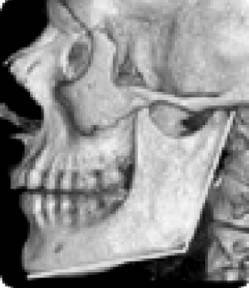

Причем, опять же, рост этого горбика она объясняет исключительно «солями» – остеохондрозом – и не связывает с изменившейся статикой своего позвоночника. В норме позвоночник, как известно, не должен быть прямым, как палка, а иметь физиологические изгибы. В частности, шейный отдел, состоящий из 7 позвонков, в норме должен быть чуть прогнутым внутрь (рис. 13).

Иллюстрация к книге — Биогимнастика для лица: система фейсмионика [i_017.jpg]

Рис. 13. Нормальная статика шейного отдела